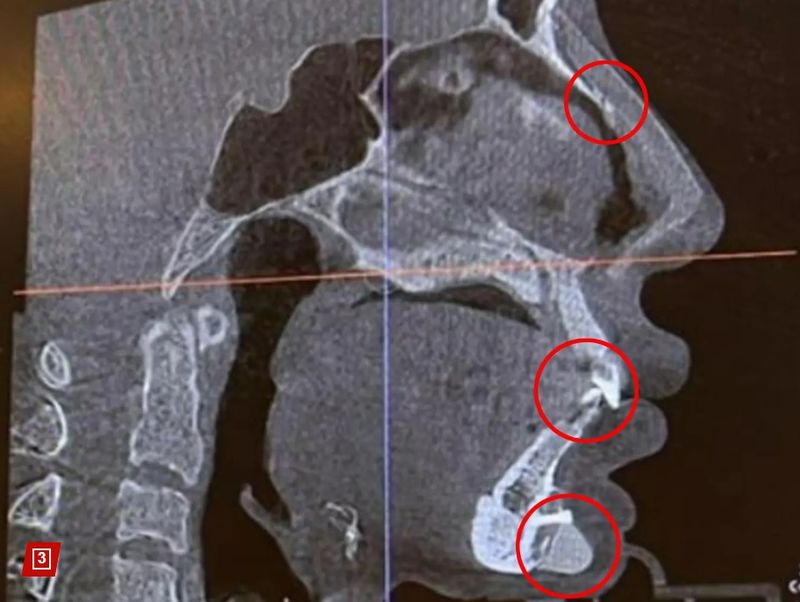

„Fața mea arată ca un puzzle!”, ar fi spus modelul în lacrimi, când a descoperit ce se află în corpul ei.

Controlul cu scanner din aeroprot ar fi semnalat prezența unui șurub chirurgical de 1 centimetru chiar sub buza de jos. Modelul crede că acel șurub a fost în corpul ei de când și-a pus o „proteză de bărbie”, în urmă cu opt ani.

„Am descoperit în mod neașteptat că am și unghii pe nas”, a mai exclamat modelul, șocată de ce a văzut că se află în corpul său.

Fang Qiyuan, în vârstă de 36 de ani, se autointitulează „fanatică a chirurgiei plastice”. Femeia are peste 19 operații plastice, între care două operații la frunte, cinci la pleoape, cinci la nas, două în bărbie și liposucție pentru repararea feței de cinci ori.